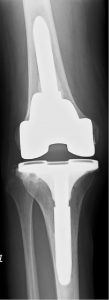

术前(左)和术后(右)关节X光图片病人三年来第一次外出手术

连续142名RA病历(201膝盖)从1997年8月22日到2011年3月16日拥有初级TKA所有程序均由单科外科医生在单一机构进行普通麻醉,所有病人都由同一名医生治病。79名病人口服类固醇,82名病人外科时服甲状腺素22名病人同时使用肿瘤消毒因子对立法处理TKATKA后,59名病人接受了生物治疗初级TKA后,106名病人单从膝部外科手术,其余36名病人额外接受低端联合外科手术,如全流节肢科全科全科全科全科节肢科全科全科全科全科全科全科全科全科全科全科全科全科全科全科全科全科全科全科全科全科全科全科全科全科全科全科全科全科全科全科全科全科全科全科全科全科全科全科全科全科全科全科全科全科全科全科全科全科全科全科全科全科全科全科全科全科全科全科全科全科全科全科全科全科全科全科全科全科全科全科全科全科全科全科全科全科全科全科全科全科全科全科全科全科全科全科全科全科全科全科全科提交者附属机构IRB(机构评审委)批准此项研究

Genesis2(Smith和Nephew,Memphis,TN,USA)在所有例子中都使用假肢类型,1997年8月首次提交115名病人(164个植入式)受难保留TKAs,25名病人(35个植入式)后稳定TKAs,2名病人修改TKAs(2个植入式)。术后第1天,所有案例都应用扩展膝盖支架,并开始ROM运动演练、连续被动运动和增强肌肉活动重生手术第二天允许使用,3周后开始爬楼梯开通T-Cane并忍受上行楼梯后,所有病人都出院

所有病人都评估成日本矫形协会评分(JOA评分)、活动ROM、X光检测结果、RA活动、户外振荡持续时间和移植累积生存率以百分位标度 JOA分数测量疼痛范围 手动肌肉测试 编译能力 爬楼梯能力疼痛标记40分 ROM标记12分 四叉肌肉强度标记20分 步行能力值20分 爬楼梯值8分JOA85或85以上评分被视为优异、70-84良好、60-69公平并低于60穷